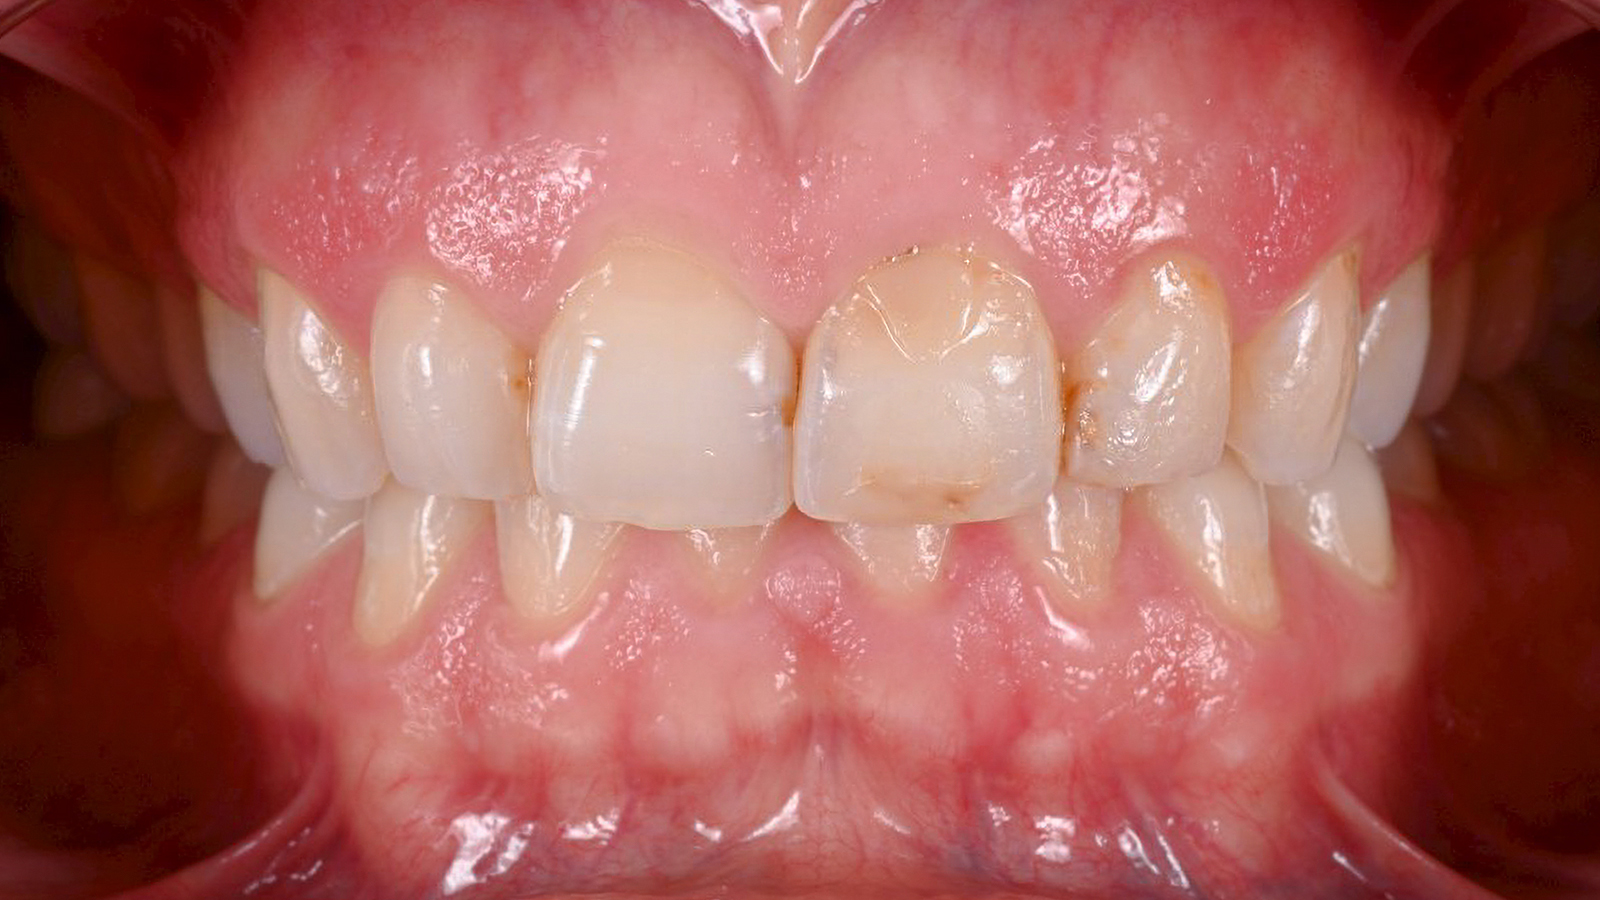

This case presented significant challenges. Several years ago, the patient fainted and fell, resulting in broken front teeth that were replaced with implants. When implants are positioned improperly, it can lead to the loss of the gum triangle between the teeth, making the implants appear thick and bulky, regardless of the quality of the ceramic.

Before